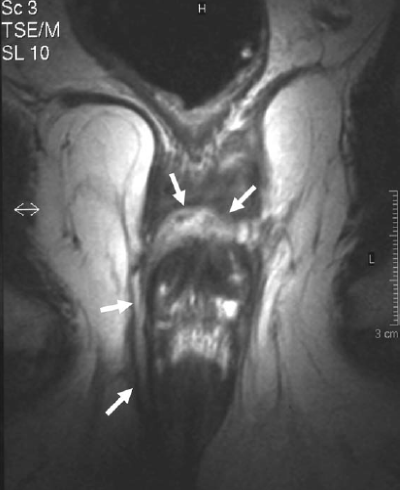

- Abscess occurs due to spread of perianal abscess or due to blood-borne infection. Fossa communicates with that of opposite side through post-sphincteric space and so horse-shoe like abscess can occur.

An ischiorectal abscess causes diffuse swelling in the ischiorectal fossa that may involve one or both sides, forming a “horseshoe” abscess.

HORSESHOE ABSCESS

These are managed by Hanley’s procedure or modified Hanley’s procedure where the abscess is openly drained through anococcygeal ligament and counter incisions over both ischiorectal fossae to control the lateral tracts.

If necessary, a seton (cutting or noncutting) is placed in the posterior midline, with subsequent definitive management taking place at a later time.